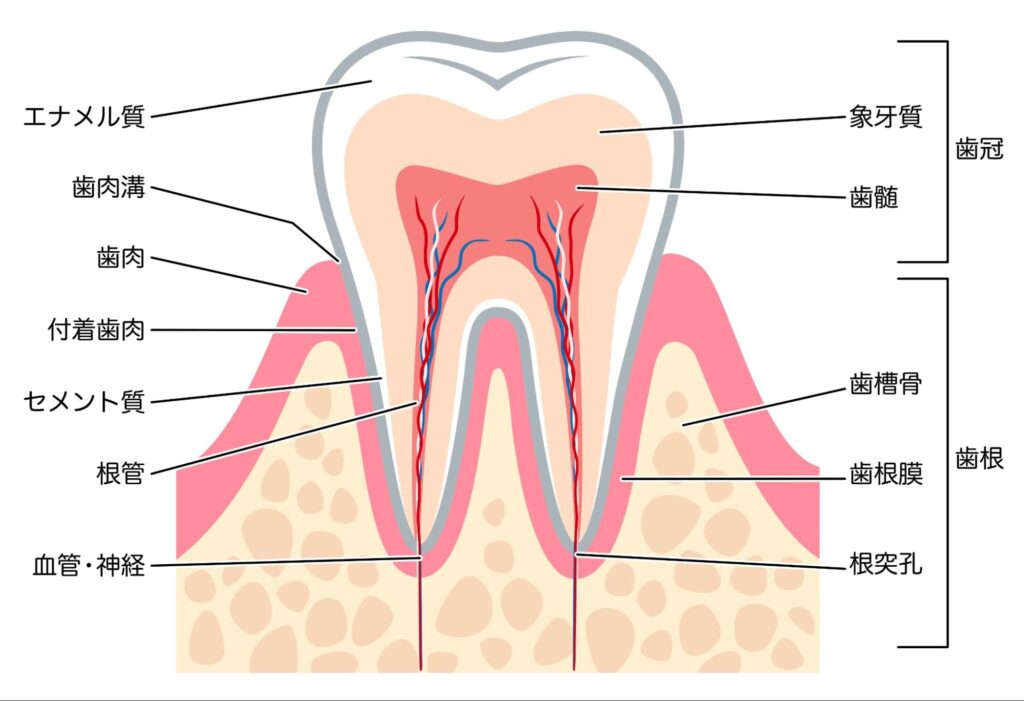

知覚過敏の痛みは、露出した象牙質にある細い管(象牙細管)を通じて、刺激が神経にダイレクトに伝わることで起こります。

- 歯ぐきが下がり、歯の根元の象牙質が露出している

- 歯の表面が摩耗・酸蝕で薄くなり、象牙質が近くなっている

虫歯は、歯の表面から内部に向かって溶けていく病気で、進行すると象牙質や歯髄に近づくにつれてしみやすくなります。

歯髄炎は、歯の神経(歯髄)が虫歯や外傷、過度な刺激などで炎症を起こした状態です。